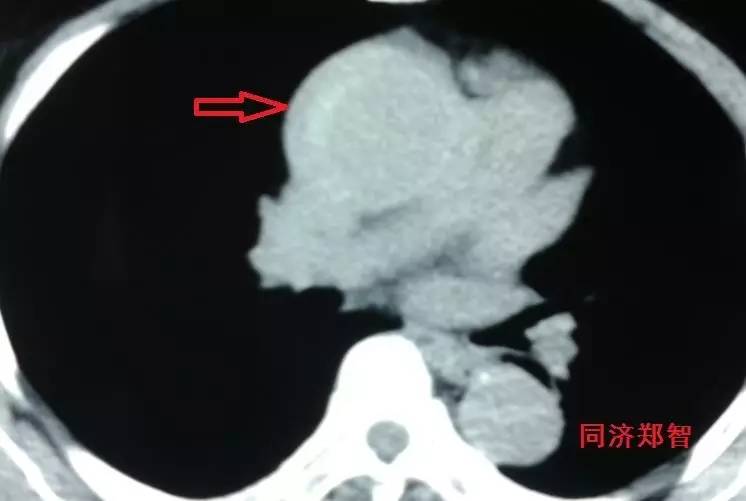

有时候平扫CT也能从血管内密度影的不同来诊断主动脉壁间血肿(图3)。平扫CT提示右肺动脉层面的升主动脉外侧为新月状稍亮的影(红箭头所示)。

图3